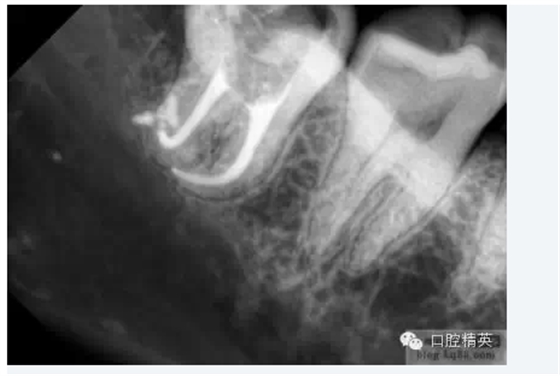

5.根管髓腔部分的預(yù)先擴(kuò)大可以幫助牙醫(yī)做出更明確的診斷。預(yù)先擴(kuò)大的根管髓腔部分可以容納較大型號(hào)的金屬根管擴(kuò)大器,X光片顯示更清晰;由于接觸頭更容易的與髓腔牙本質(zhì)接觸,電子根尖定位器的顯示也更明確。

當(dāng)根管的髓腔向2/3的擴(kuò)大完成以后,臨床牙醫(yī)即可順利的進(jìn)行根尖1/3的擴(kuò)大及最后精細(xì)完成。因?yàn)榇蟛糠值难栏鶑澢胺植娑及l(fā)生在該區(qū)域,所以,應(yīng)先應(yīng)用小型的不銹鋼可彎曲的根管擴(kuò)大針對(duì)其進(jìn)行小心而精密的探測(cè),以獲得更詳細(xì)而準(zhǔn)確的診斷資料。

測(cè)量與調(diào)整

當(dāng)經(jīng)過(guò)精確的測(cè)量與適當(dāng)調(diào)整后,牙醫(yī)即可確定該牙齒的根管系統(tǒng)的預(yù)備已成功完成,可以進(jìn)行下一步的治療。經(jīng)典的根尖1/3預(yù)備標(biāo)準(zhǔn)為:至少20號(hào)擴(kuò)孔銼能順利到達(dá)距根尖孔0.5mm位置,且經(jīng)過(guò)徹底的根管清理,保證根管內(nèi)無(wú)碎霄殘留。 采用梯度為0.02mm的國(guó)際標(biāo)準(zhǔn) (ISO 0.02) 擴(kuò)孔銼對(duì)根尖1/3進(jìn)行測(cè)量與調(diào)整。首先應(yīng)大體完成根管尖端1/3的擴(kuò)大再進(jìn)行精確的修整,當(dāng)合適的手用或機(jī)用根管擴(kuò)大工具能順利地進(jìn)出根管尖端1/3時(shí),牙醫(yī)方可基本確定所需的工作長(zhǎng)度已達(dá)到,可以進(jìn)行進(jìn)一步的修整。 為了更進(jìn)一步確定根管擴(kuò)大針的位置、直徑都正確地反映了實(shí)際的根尖位置及大小,臨床牙醫(yī)還必須對(duì)根管進(jìn)行調(diào)整。此過(guò)程需經(jīng)過(guò)反復(fù)的應(yīng)用各種類型的擴(kuò)根器械對(duì)根管進(jìn)行挫磨、修整,直到更大型號(hào)的擴(kuò)根器械也能較為順利地進(jìn)出各個(gè)根管并達(dá)到應(yīng)有長(zhǎng)度。但應(yīng)注意,在所采用的較大型號(hào)的擴(kuò)根器械與20號(hào)擴(kuò)孔銼所能進(jìn)入根管的長(zhǎng)度之差不應(yīng)超過(guò)0.5mm。并且,擴(kuò)好的根管應(yīng)能容納20號(hào)擴(kuò)孔銼在其中順利旋轉(zhuǎn)。